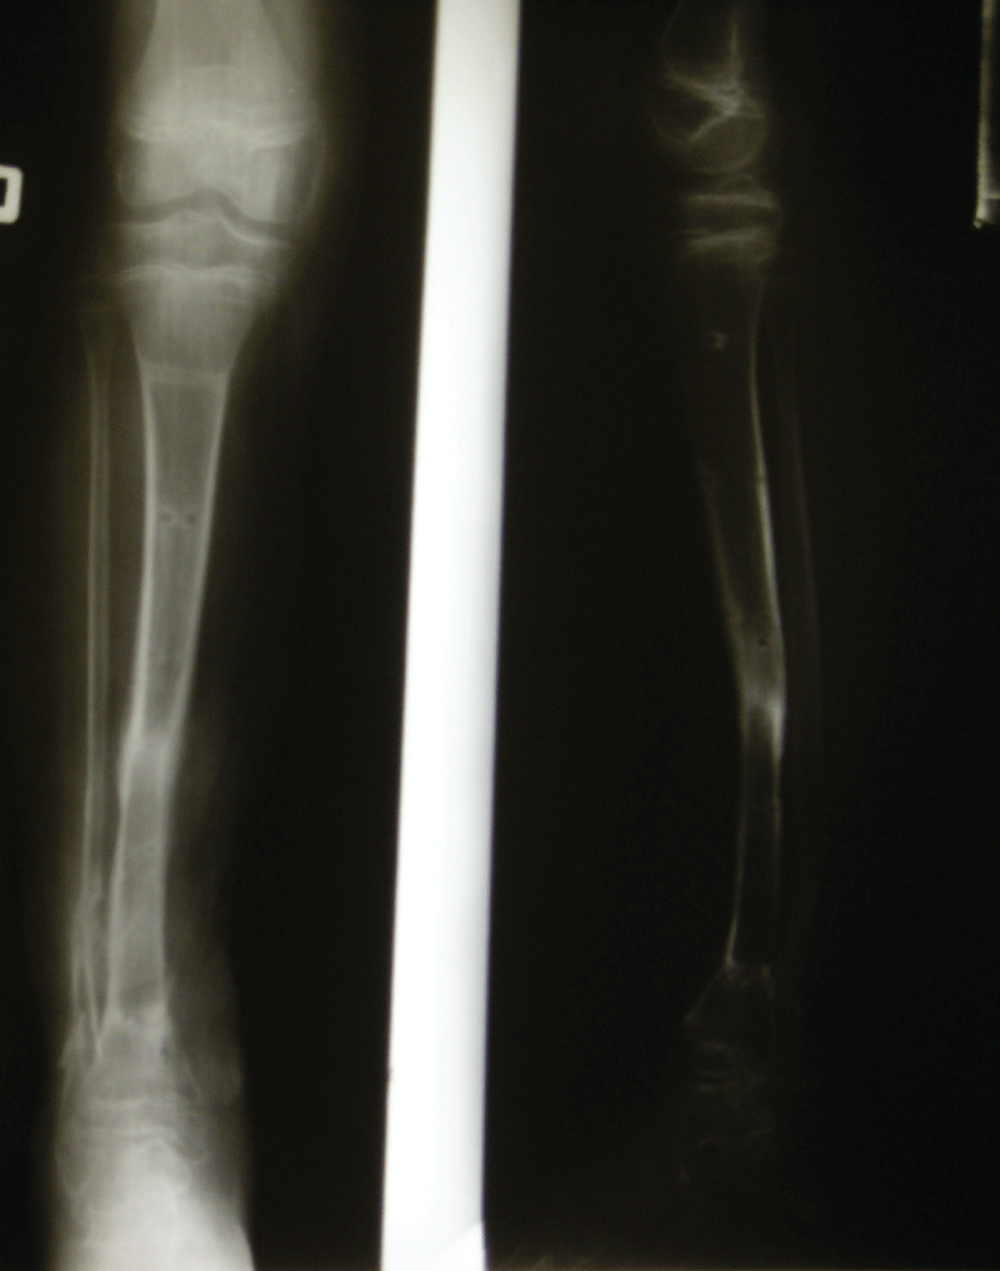

The deep infection on the right side required several surgical procedures with debridement of infected tissues and resulted in 10 cm segmental diaphyseal bone defect of distal tibia with accompanying muscle and skin loss on the same level (Figure 3). The remaining stump of the left shin was not suitable for the use of prosthesis and was finally planned for a below knee amputation on selected level. However the remaining distal part of left leg was intended to be used as a donor complex tissue for reconstruction of segmental defect on right tibia.

Figure 3: Segmental diaphyseal bone defect of distal tibia with accompanying muscle and skin loss

After determining the level of amputation the first stage of the reconstruction procedure was performed. It included dissection of pedicled bone muscle and skin segment on left leg and placing it into the defect on right side (Figure 4, Figure 5).

The temporary stabilisation with modified Ilizarov fixator was performed. After 4 weeks a second stage of reconstruction was done with final formation of below knee stump on left side and change of configuration of Ilizarov fixator on right side (Figure 6). After consecutive 3 months the soft tissue flap healed and union between the transported bone segment and the defect on right tibia was observed on X-ray that allowed the removal of the external fixator (Figure 7).